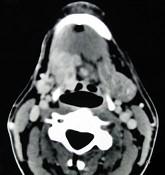

问题 女,40岁,口腔内长一肿块约九个月,逐渐感疼痛,PE:肿块呈淡红色,表面有浅溃疡,CT如图所示,最可能诊断为()

选项 A.舌根癌 B.扁桃体癌 C.扁桃体肥大 D.口底癌 E.腺样体增生

答案 A